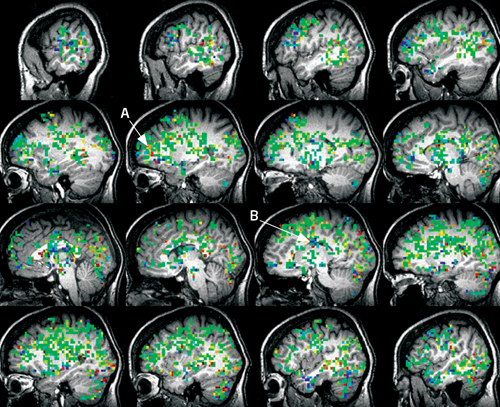

This Is Your Brain On Orgasm

Kayt Sukel masturbated for a fMRI:

Over 30 areas of my brain are activated as I move from start to finish, including those involved in touch, memory, reward and even pain. As [researcher Barry] Komisaruk expected, the imagined clitoral touches and Kegel exercises activated the same brain areas as real ones, albeit with somewhat less blood flow. The [prefrontal cortex], however, showed more activation when touches and pelvic squeezes were imagined compared with those that were real. He suggests this heightened activation may reflect imagination or fantasy, or perhaps some cognitive process that helps manage so called "top-down" control – the direct regulation by the brain of physiological functions – of our own pleasure.

(Image: Kayt Sukel's brain at the moment of orgasm. "You can see from the extent of activity that an orgasm is a whole-brain experience. Activation in the prefrontal cortex (A) is clearly visible, as well as activity in the anterior cingulate cortex (B), thought to be involved in the experience of pain.")